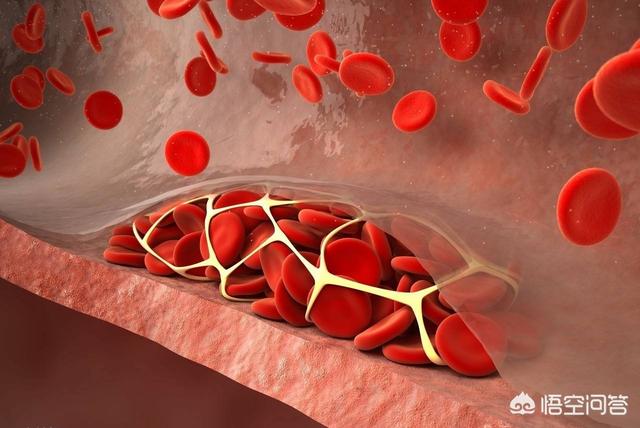

プラークは、静脈プラーク、動脈プラークを持って、それは複数の病因因子の役割にある、沈殿物の脂質化のために、単刀直入に言えば、つまり、あなたがより多くのグリース、消化と使用することはできません、血中脂質4と他の多因子の影響下で、内膜に損傷を与え、血管の内層に沈着し、黄色のアテローム性脂質のコアの形成、および最終的に線維性キャップが持続的な炎症にさらされている場合、通常は非常に安定している脂質のコア、上の線維性コアの形成にある攻撃は、飲酒、怒り、夜更かし、少ない水を飲むなど、線維性キャップが破裂し、プラークが流出し、血液中の血小板が結婚フラッシュ、血栓と呼ばれるトラブルメーカーの子供を出産し、この子は、血管をブロックするために悪いことをすることに特化し、トラブルを作るためにさまよう、血管の内腔に血栓が同時に狭くなるだけでなく、破裂、急性心脳血管イベント、脳卒中、心筋梗塞、肺塞栓症、腎不全、静脈瘤などを誘発する。などである。したがって、プラークを除去することは、血管の詰まりを取り除くだけでなく、急性心血管系および脳血管系イベントを予防することにもなり、誰もが関心を寄せている。

動脈プラークは、複数の病因因子の影響下にある動脈内膜の損傷によって引き起こされる一連の炎症反応であり、後に二次的なアテローム性プラークが生成される。プラークの形成は人体にとってより有害であり、同時に血管の内腔を狭くし、破裂して急性心血管系イベントを誘発することもある。したがって、プラークを除去することは血管の詰まりを解消するだけでなく、急性心血管系イベントを予防することにもなり、これはすべての患者の心臓の鼓動である。プラークの治療には、血中脂質、血圧、血糖値などのコントロール、減塩、低コレステロール食、運動量の増加、禁煙、アルコール制限などの悪い生活習慣の改善など、病気の原因から始めるか、上記の治療の上に薬物療法を行うことができます。薬の選択は、アトルバスタチン、レセルプルバスタチンなどのスタチン系薬剤がアテローム性プラークの治療によく使用されます。具体的な治療計画は専門医の指導のもとに立てるべきである。

しかし、これらの治療を行っても、動脈プラークを除去することは困難である。多くの患者はスタチンがプラークを逆転させると聞いたことがあるが、プラークを逆転させるというのは、脂質をプラークの外に移動させ、粥腫性プラークを縮小させ、その安定性を高め、破裂の危険性を減少させ、心血管イベントの危険性を低下させることを意味するのであって、いわばプラークを血管から完全に除去することではないし、一度プラークが形成されるとそれを除去することはほとんど不可能である。

初期のプラーク形成は、脂肪の蓄積が一連の炎症反応を引き起こし、実際には、脂肪は常に酸化変性、粥状物質の形成であり、これらの物質は、血管の正常な構造を破壊し、血管の一部となり、この時点で、脂質化された材料は、通常、ソフトスポットと呼ばれる液体の状態にほとんどである。

ソフトスポットの脂質化した物質は、皮膚感染症が膿を出すと線維化し痂皮化するように、時間の経過とともに壊死することがある。また、カルシウムが沈着すると石灰化が起こり、プラークが硬くなり、血管収縮機能がより低下する。このようなプラークはハードスポットと呼ばれる。

プラークが血管に与えるダメージや影響は、プラークの形成段階によって異なることがわかる。 初期のプラークは血管の構造に深刻なダメージを与えておらず、除去したり元に戻したりできる可能性があるが、ソフトプラークやハードプラークはすでに血管の正常な構造を置き換えてしまっている。プラークを完全に除去することは不可能であり、プラークの継続的な成長を止め、遅らせることが必要である。